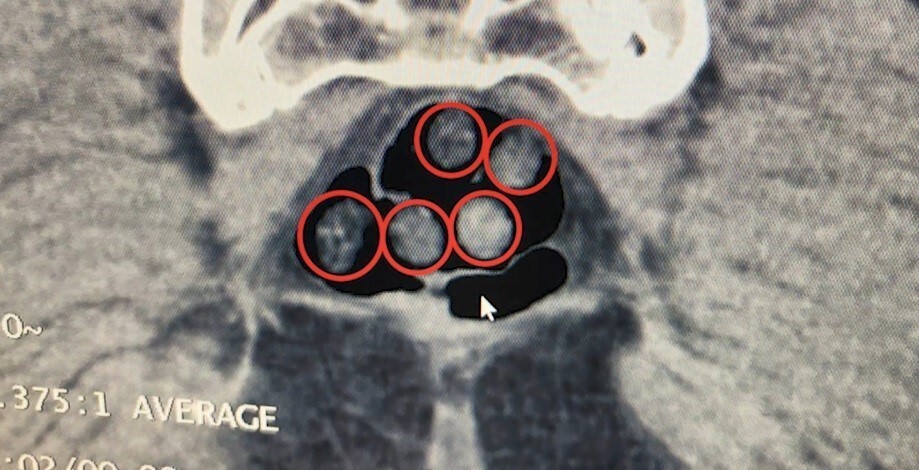

İkinci operasyonda ise Tatvan'da durdurulan bir otobüste yolcu olarak seyahat eden yabancı uyruklu 2 şahıs gözaltına alındı. Tatvan Devlet Hastanesinde yapılan röntgen ve tomografi incelemelerinde, şahısların mide ve bağırsaklarında çok sayıda yabancı cisim tespit edildi.

Tıbbi müdahale sonucu şahısların yuttuğu 14 kapsül ve üzerlerinden çıkan 36 kapsül olmak üzere toplam 50 kapsül / 385 gram metamfetamin ele geçirildi.

TATVAN DEVLET HASTANESİNDE YAPILAN RÖNTGEN VE TOMOGRAFİ İNCELEMELERİNDE, ŞAHISLARIN MİDE İLE...